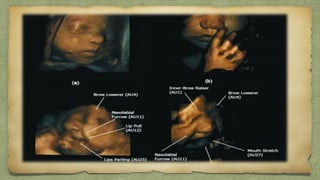

๏ฑSaggital profile view

๏ฑAxial view Orbit

๏ฑAxial View Maxilla/Mandible

๏ฑNose-Lip view

ABNOMALITESโ€ฆ.

Retrognathia

mm=Ges age

Frontal Bossing

Slopped Forehead

Agnothia

Cleft lip

Macroglossia